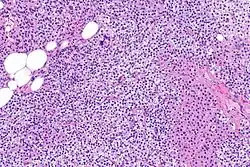

Parathyroid glands are normally composed of chief cells, adipocytes and scattered oxyphil cells.[27][14] Chief cells are thought to be responsible for the production, storage and secretion of parathyroid hormone. These cells appear light and dark with a prominent Golgi body and endoplasmic reticulum. In electron micrographs, secretory vesicles can be seen in and around the Golgi and at the cell membrane. These cells also contain prominent cytoplasmic adipose.[27][14] Upon onset of hyperplasia these cells are described as having a nodular pattern with enlargement of protein synthesis machinery such as the endoplasmic reticulum and Golgi. Increased secretory vesicles are seen and decreased intercellular fat is characteristic.[27][24] Oxyphil cells also appear hyperplasic however, these cells are much less prominent.

Biochemically, there are changes in function between normal and nodular hyperplastic parathyroid glands. These changes involve proto-oncogene expression and activation of proliferative pathways while inactivating apoptotic pathways.[28] In nodular parathyroid tissue increased expression of TGF-a, a growth factor, and EGFR, its receptor, results in aggressive proliferation and further downregulation of vitamin D receptors, which act to suppress hormone secretions.[25][8][28] Furthermore, the proliferative marker, Ki67 is seen to be highly expressed in the secondary nodular hyperplastic state.[28][25] Tumour suppressor genes have also been highlighted as being silenced or degraded in nodular hyperplastic parathyroid tissue.[8][28] One such gene, p53, has been shown to regulate multiple tumour suppressor pathways and in tumorigenesis can be degraded by b-catenin. This pathway, in some aspect, is mediated by CACYBP, which is highly expressed in nodular parathyroid hyperplasia.[28]

Primary hyperplasia of the parathyroid gland, results from both hypocalcaemia and increased phosphate levels by decreasing expression of calcium sensing receptors and vitamin D receptors at the parathyroid gland.[8][4] These decreases in receptor expression lead to hyperfunctioning of the parathyroid. Hyperfunction of the parathyroid gland is thought to exacerbate primary hyperplasia which evolves further to a secondary more aggressive hyperplasia. Histologically, these hyperplasic glands can be either diffuse or nodular.[24] Primary hyperplasia, usually resulting in diffuse polyclonal growth is manly related to reversible secondary hyperparathyroidism. Secondary hyperplasia of the parathyroid gland is more often a nodular, monoclonal growth that sustains secondary hyperparathyroidism and is the catalyst in the progression to tertiary hyperparathyroidism. Nodular hyperplastic glands in tertiary hyperparathyroidism are distinctly larger in both absolute size and weight up to 20-40-fold increases have been reported.[25][26][24]